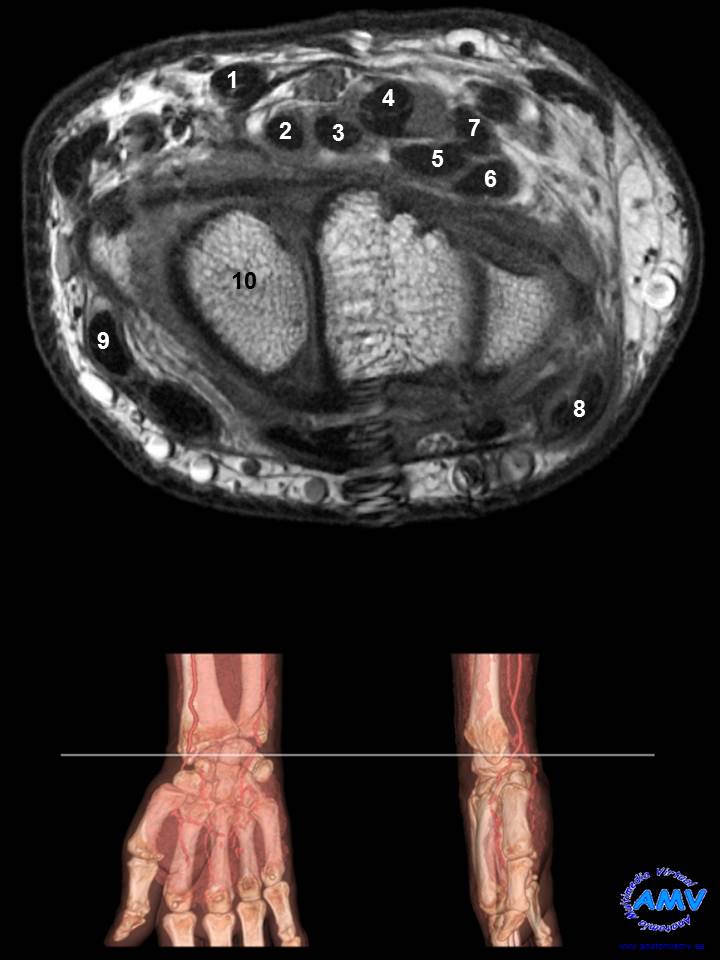

RMN Axial de Muñeca

ms_rmn_09.jpgIndique que estructura se señala con el número correspondiente:

El nº 1 señala al tendón del músculo .

El nº 2 señala al tendón del músculo .

El nº 3 señala al tendón del músculo .

El nº 4 señala al tendón del músculo .

El nº 5 señala al tendón del músculo .

El nº 6 señala al tendón del músculo .

El nº 7 señala al tendón del músculo .

El nº 8 señala al tendón del músculo .

El nº 9 señala al tendón del músculo .

El nº 10 señala al hueso .